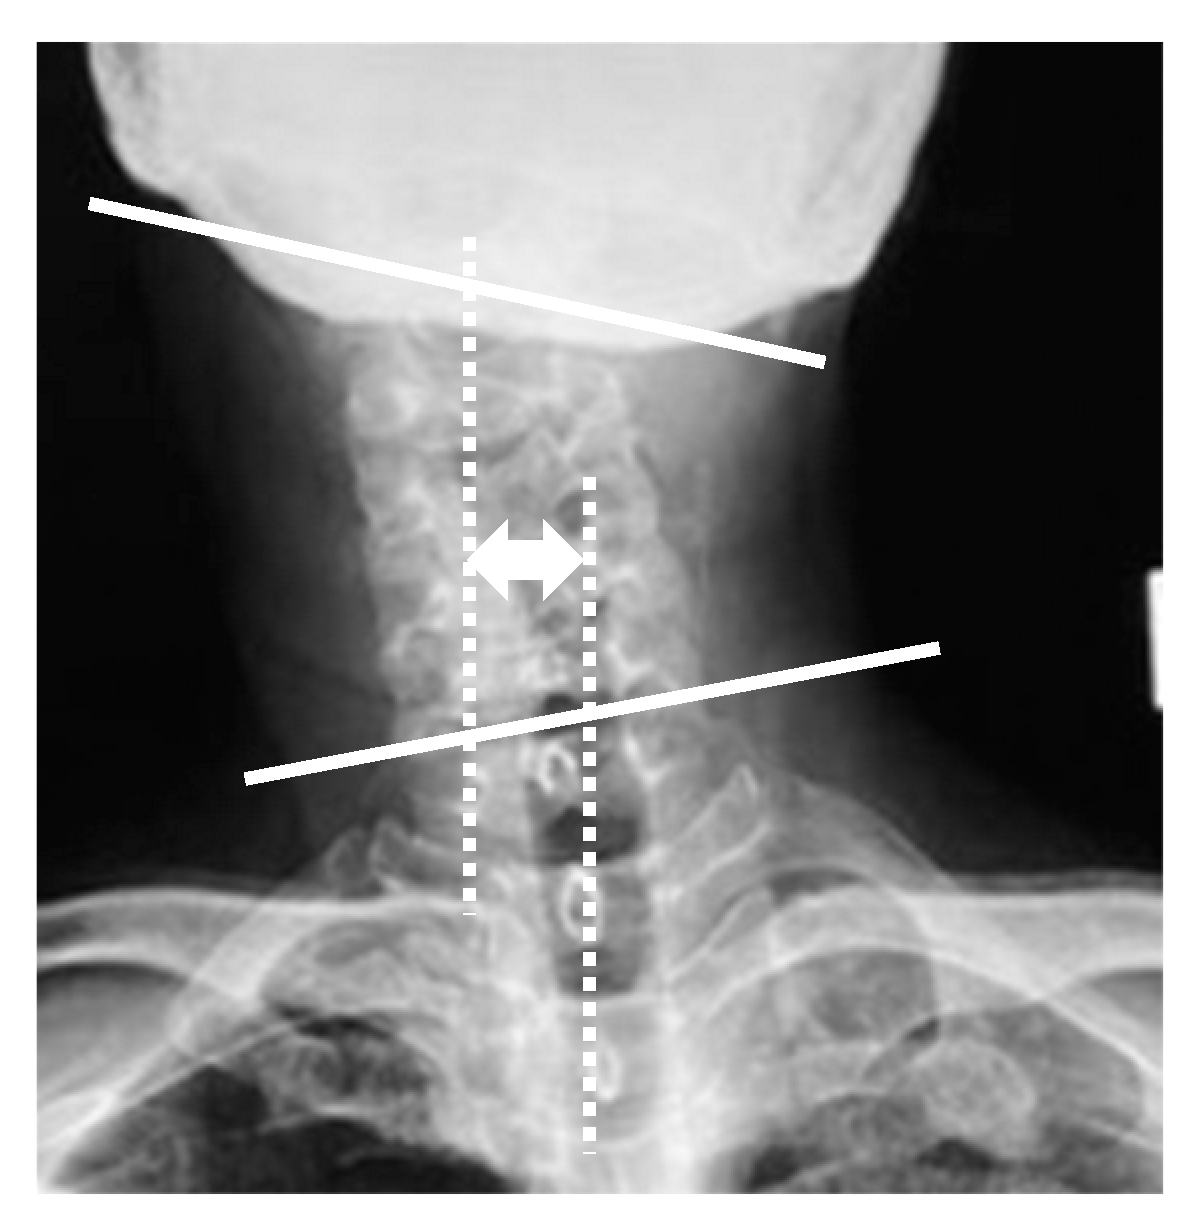

Radiographic parameters included: cervicomandibular angle (CMA) for head tilt; C2 to T1 distance for lateral shift of neck; clavicle angle for shoulder balance; central sacral vertical line (CSVL) for coronal global balance; C2–7 angles (neutral, flexion, extension) for cervical alignment and range of motion on the sagittal plane; C2–7 sagittal vertical axis (C2–7 SVA); and C7 SVA for whole spinopelvic sagittal alignment. CMA was defined as the angle between a line connecting the lower margins of the mandibular angle and the superior endplate of C7 on the anterior and posterior radiographs. The C2 to T1 distance was defined as the distance between the vertical line from the center of the C2 vertebra and that of the T1 vertebra on the anterior and posterior radiographs (Figure 1). C2–7 angles were measured by determining the C2–7 angles between the inferior endplate of C2 and the superior endplate of C7 vertebra in neutral, flexion, and extension positions on the lateral radiographs. The cervical range of motion was calculated by subtracting flexion from extension C2–7 angles. CSVL was defined as the distance between the vertical line from the midline of the sacrum and that of the C7 vertebra, and clavicle angle was defined as the angle between the horizontal line and tangential line connecting the highest two points of each clavicle on the standing anterior and posterior radiographs. C7 SVA was defined as the distance between the C7 plumb line and the posterior superior corner of the S1 vertebra, and C2–7 SVA was defined as the distance between the C2 plumb line and the posterior superior corner of the C7 vertebra on the standing lateral radiograph (Figure 2). Measurements were taken by three spine surgeons with more than 10 years of experience at our institution.

Figure 1.

Radiographic parameters: cervicomandibular angle and C2 to T1 distance.

CMA was defined as the angle between a line connecting the lower margins of the mandibular angle and the superior endplate of C7 on the anterior and posterior radiographs (white lines). The C2 to T1 distance was defined as the distance between the vertical line from the center of the C2 vertebra and that of the T1 vertebra on the anterior and posterior radiographs (white dotted lines).